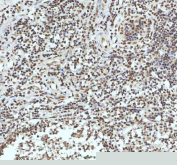

Immunohistochemical staining of IRF2BP1 using anti-IRF2BP1 antibody. IRF2BP1 was detected in a paraffin-embedded section of human ovarian cancer tissue. Heat mediated antigen retrieval was performed in EDTA buffer (pH 8.0, epitope retrieval solution). The tissue section was blocked with 10% goat serum. The tissue section was then incubated with 2 ug/ml rabbit anti-IRF2BP1 antibody overnight at 4oC. Peroxidase Conjugated Goat Anti-rabbit IgG was used as secondary antibody and incubated for 30 minutes at 37oC. The tissue section was developed using an HRP secondary and DAB substrate.